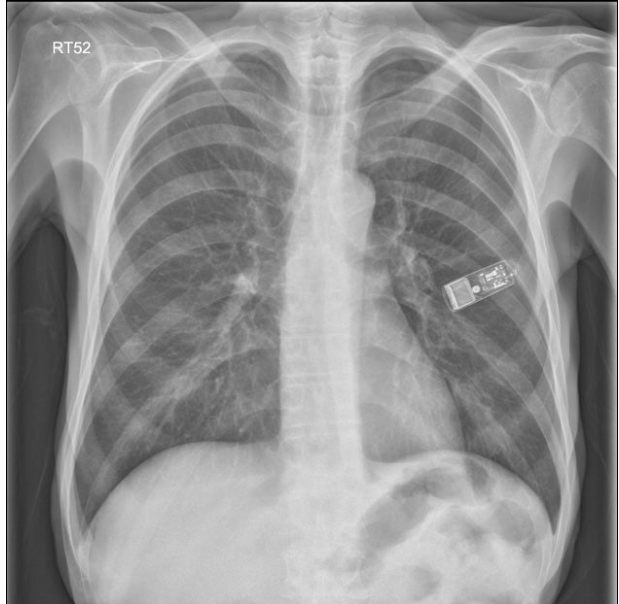

이식형 심장 사건 기록기 (ILR) 은 USB 메모리 스틱과 비슷한 납작한 모양의 작은 물체입니다. single-lead 심전도를 기록, 저장할 수 있는 기능을 가지고 있습니다. (최대 3년) 특정 서맥, 빈맥 부정맥이 발생할 경우 자동으로 심전도를 저장할 수 있습니다. 환자가 증상이 있을 때 추가적으로 심전도를 기록할 수 있습니다.

보통 left parasternal region 에 세로로 이식합니다. 최근에는 크기가 작아져 외래에서 피하주사하듯 간단히 이식이 가능해졌습니다. (Injectable ILR, Medtronic Reveal LINQ)